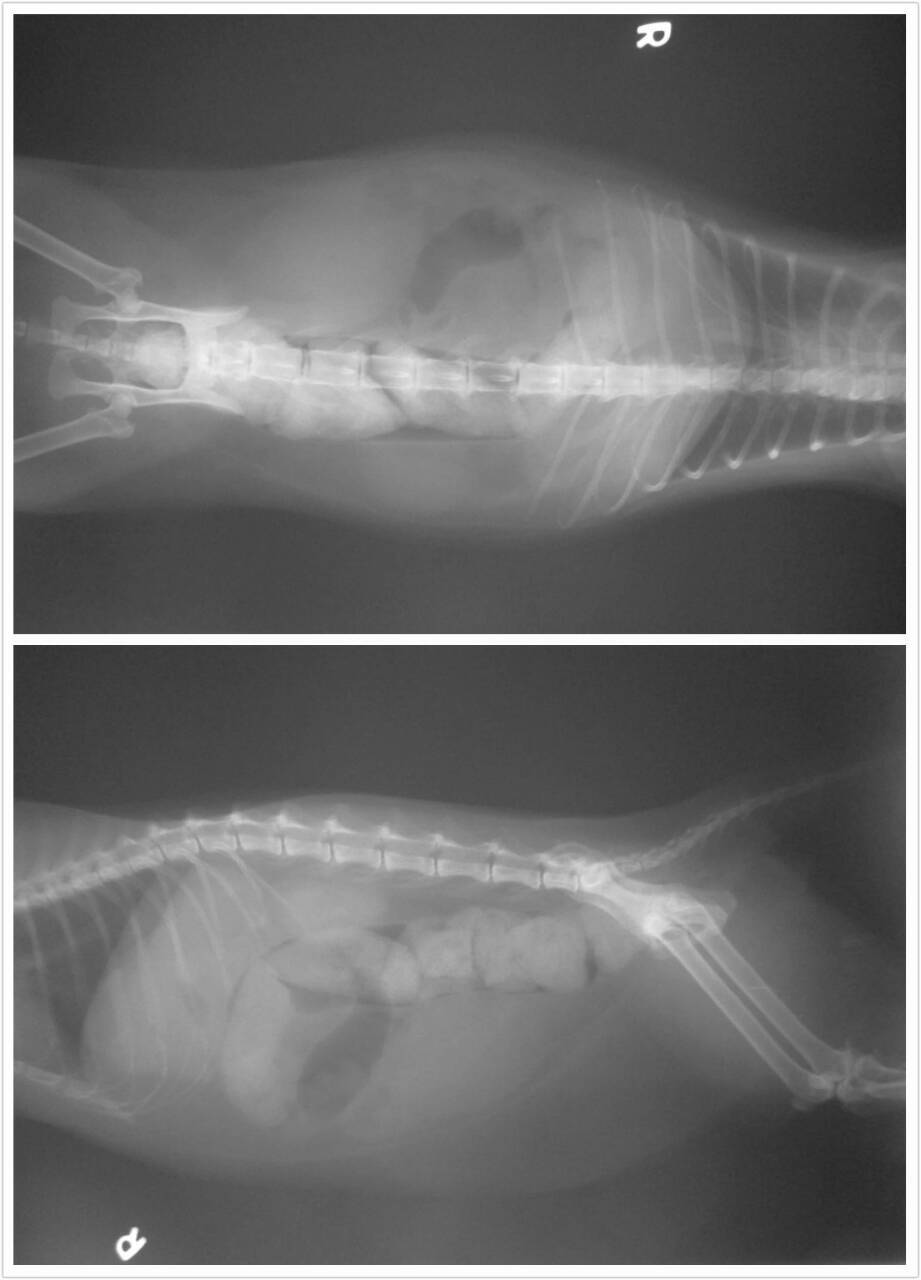

貓咪到院時後軀都是尿液, 醫生說有有漏尿的現象,尾巴無痛覺反應且不會擺動,可能薦椎神經有損傷,腹部觸診會痛, 有積糞可能也無法排便, 臀部剃毛發現有外傷瘀血跡象,初步驗血有白血球數及肝指數過高的現象,有發炎及肝損傷的問題,紅血球稍低, 此外有牙結石及齒齦炎,貓二合一檢驗為貓愛滋陽性,此貓可能有遭撞擊以致薦椎神經及肝臟損傷.

醫院目前已先給點滴及藥物治療, 肝藥(肝營養劑幫助肝修復), 止痛劑及抗生素 , X光片下有大膀胱及積糞, 目前觀察中

1/6 送醫後醫師初步診斷為下:因到院時後驅都是尿液,有漏尿現象呈現尿失禁狀態,尾巴無痛覺反應且不會擺動,可能薦椎神經有受損,腹部觸診會痛,有積糞,可能也無法排便,臀部剃毛後發現有外傷及瘀血跡象,初步驗血有白血球數及肝指數過高的現象,有發炎及肝損傷的問題,紅血球稍低,此外有牙結石及齒齦炎,貓二合ㄧ檢驗為貓愛滋陽性,貓咪可能有遭撞擊以致薦椎神經及肝臟受損...

初步醫生先給予點滴及藥物治療(肝藥,止痛劑及抗生素,還有止血劑),X光片下確定膀胱有漲大及積糞,所以先給予擠尿和浣腸,以減緩不適